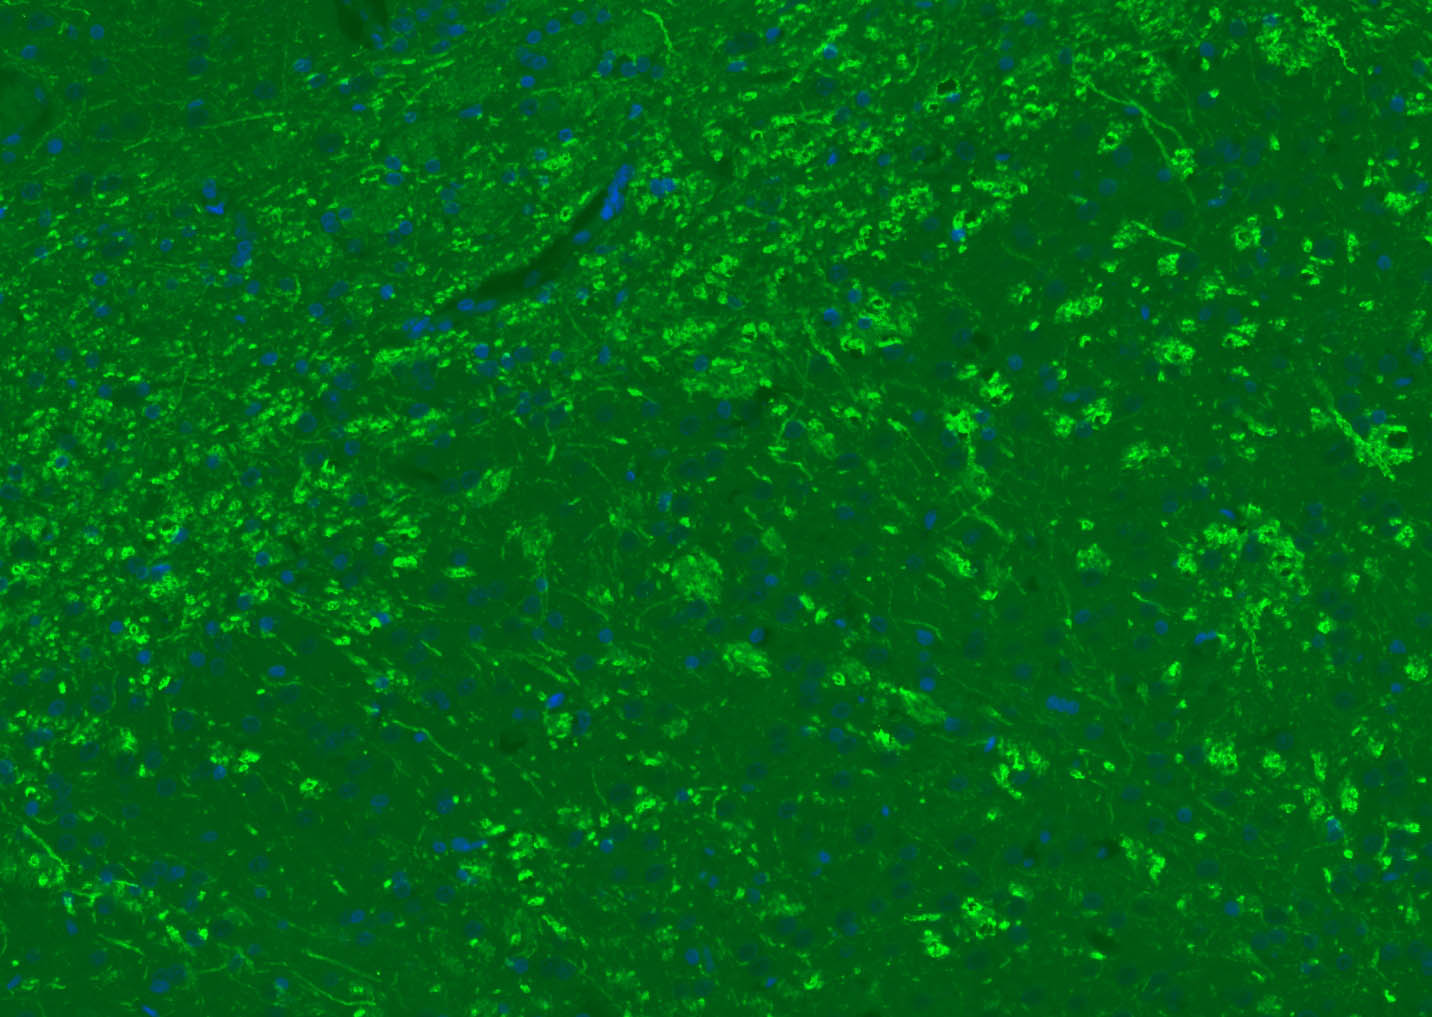

The protein encoded by the classic MBP gene is a major constituent of the myelin sheath of oligodendrocytes and Schwann cells in the nervous system. However, MBP-related transcripts are also present in the bone marrow and the immune system. These mRNAs arise from the long MBP gene (otherwise called "Golli-MBP") that contains 3 additional exons located upstream of the classic MBP exons. Alternative splicing from the Golli and the MBP transcription start sites gives rise to 2 sets of MBP-related transcripts and gene products. The Golli mRNAs contain 3 exons unique to Golli-MBP, spliced in-frame to 1 or more MBP exons. They encode hybrid proteins that have N-terminal Golli aa sequence linked to MBP aa sequence. The second family of transcripts contain only MBP exons and produce the well characterized myelin basic proteins. This complex gene structure is conserved among species suggesting that the MBP transcription unit is an integral part of the Golli transcription unit and that this arrangement is important for the function and/or regulation of these genes.

| 应用 | 已检合格种属 | 预测种属 | 推荐稀释比例 |

|---|---|---|---|

| WB | Mouse, Rat | Human, Rabbit, Pig, Sheep, Cow, Dog, Horse | 1:1000-5000 |

| IHC-P | Human, Mouse, Rat | Rabbit, Pig, Sheep, Cow, Dog, Horse | 1:500-2000 |

| IHC-F | Human, Mouse, Rat | Rabbit, Pig, Sheep, Cow, Dog, Horse | 1:500-2000 |

| IF | Human, Mouse, Rat | Rabbit, Pig, Sheep, Cow, Dog, Horse | 1:500-2000 |

| Flow-Cyt | Rat | Human, Mouse, Rabbit, Pig, Sheep, Cow, Dog, Horse | 1:100-200 |

交叉反应: Human, Mouse, Rat (predicted: Rabbit, Pig, Sheep, Cow, Dog, Horse)